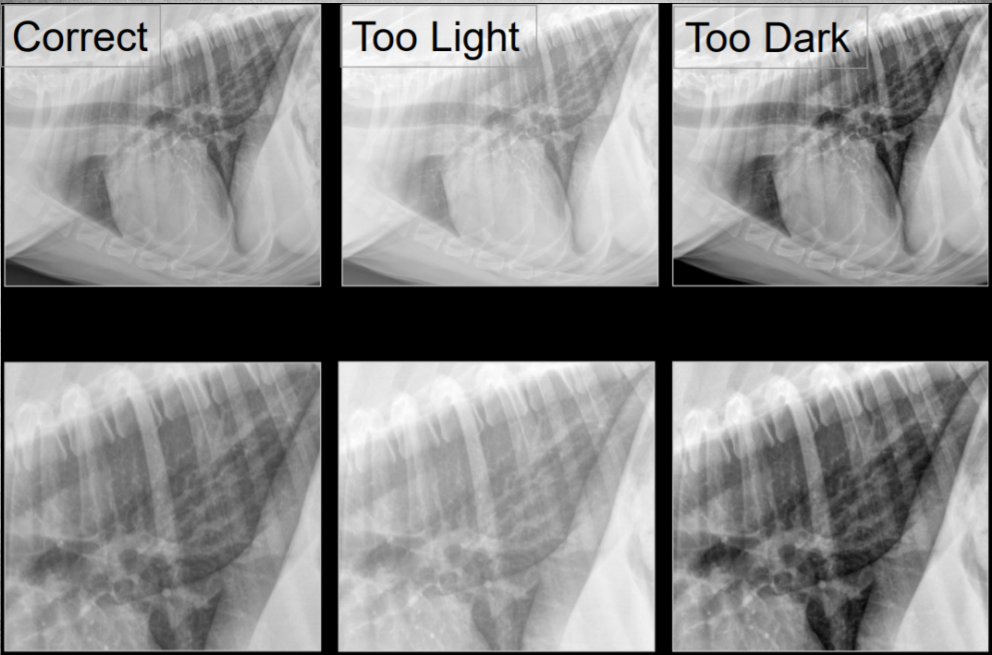

Describe radiographic parameters for thorax.

High Kv, low mAs

– As much gray tones as possible, less contrast (black, white).

(higher Kv = lower contrast)

(mAs for brightness)